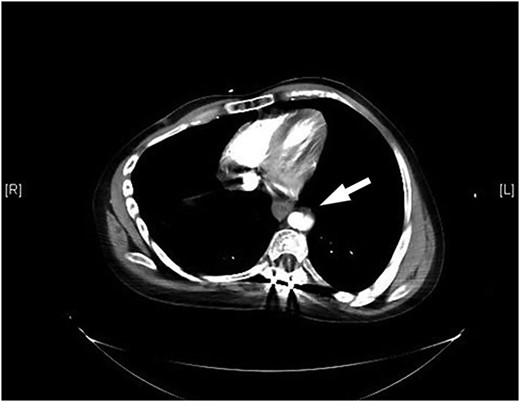

The patient returned to the hospital less than a week later in extremis. He had severe back pain and was diaphoretic. The patient was hypotensive and tachycardiac. He had no femoral pulses. Repeat CT scan revealed extension of the aortic injury in the abdominal aorta with no flow in the iliac (Figs 2–4). The patient was emergently taken to the operating room (OR) where the aorta, iliac and femoral vessels were unable to hold sutures. We were unable to repair this patient's aorta. Post-operatively, we spoke with the family, and the patient was allowed to expire.

Note contrast in the distal aorta but no contrast in the iliac arteries.